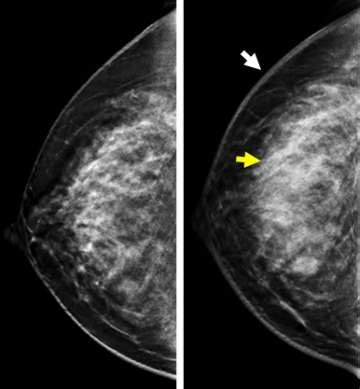

So, why is ultrasound for inflammatory breast cancer such a big deal? Well, traditional mammograms, while excellent for detecting many types of breast cancer, can sometimes miss IBC. This is because IBC often causes diffuse changes throughout the breast, like skin thickening and increased fluid in the breast tissue, rather than a distinct mass. Ultrasound, on the other hand, is fantastic at visualizing these subtle changes. It uses sound waves to create detailed images of the breast’s internal structures. For IBC, an ultrasound can help doctors see:

Think of it this way: a mammogram is like a general overview, while an ultrasound is like a high-resolution zoom lens that can pick up finer details. This makes it an indispensable tool, especially when a patient presents with symptoms suggestive of IBC. Doctors might order an ultrasound even if a mammogram appears normal, simply because the clinical signs are concerning. The ability of ultrasound to differentiate between solid masses, cysts, and areas of inflammation is also a significant advantage. For IBC, the inflammation and blockage of lymphatics are key features that ultrasound can highlight better than other methods. This detailed imaging allows for a more accurate assessment of the extent of the disease and helps in distinguishing IBC from other conditions that might cause similar-looking symptoms, like benign infections. Ultimately, the goal is to get the most accurate diagnosis as quickly as possible, and ultrasound plays a starring role in achieving that for patients suspected of having inflammatory breast cancer.

Now, let’s get into the nitty-gritty of interpreting inflammatory breast cancer ultrasound results. This is where the radiologist, that specialized doc we just talked about, really earns their stripes. They’re looking for specific patterns and characteristics that are indicative of IBC. As we’ve mentioned, ultrasound for inflammatory breast cancer is key because IBC often presents with diffuse changes rather than a discrete lump. So, what exactly are they scrutinizing on those images?

• Skin and Subcutaneous Tissue Thickening: The normal skin thickness is usually just a couple of millimeters. In IBC, this can significantly increase, often exceeding 2-3 mm, and appear irregular. Ultrasound is excellent at precisely measuring this thickness and noting any architectural distortion.

• Mammography: This is your standard breast screening tool. It uses X-rays to create images. Mammograms are great at detecting calcifications and distinct masses, which are common in other types of breast cancer. However, with IBC, which often lacks a distinct lump and causes diffuse skin thickening and inflammation, a mammogram might appear normal or show subtle changes that aren’t definitive. So, while it’s often done, it might not be the most sensitive tool for IBC itself.